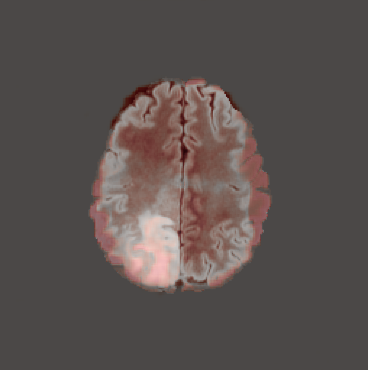

When computing with Eq. (9), the sum of the two components may not produce a perfectly coherent result. However, the incoherence is resolved by the next diffusion step, which fuses the two components better. This would not be the case if we simply computed with DDPM and then applied the mask only at the end of the sampling process. An illustration of this effect is presented in Figure 3, where we can observe how the normal image, generated by applying the mask solely at the conclusion of the sampling process (b), exhibits some artifacts and lacks a seamless transition between the edited and unedited regions.

In Figures 2 and 4 we display examples of healthy images and anomaly maps obtained with the different approaches. We can observe that f-Ano GAN is not able to generate credible counterfactuals and generally produces images of poor quality and unrealistic appearance. On the other hand, the approaches based on diffusion models are able to create more high-quality results. However, the ones obtained with CG and CFG seem to present some artifacts, which may not only impact the realism of the counterfactual examples but also the precision of the anomaly maps obtained from them. In order to better quantify the capability of these methods to accurately segment pathological areas, we compute the Dice scores of the anomaly maps they generate.